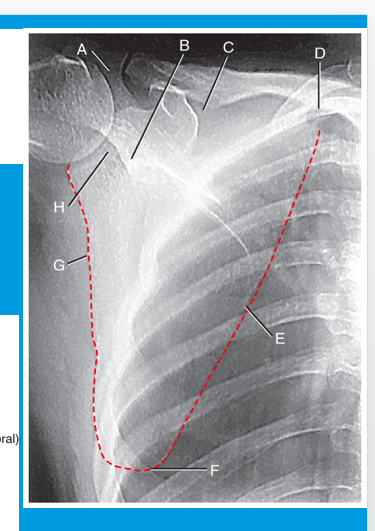

acromion

A

neck of scapula

B

suprascapular notch

C

superior angle

D

medial (vertebral) border

E

inferior angle

F

lateral (axillary) border

G

glenoid fossa

H